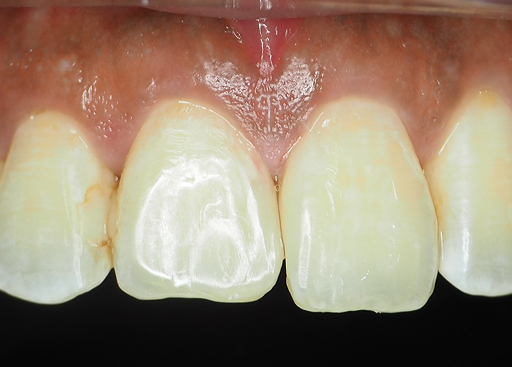

We use a digital intraoral scan to capture a detailed 3D image of your teeth and gums in real time. This helps us detect hidden issues such as cracks, gum problems, or early decay that may be causing your toothache.

For: compromised tooth structure

Note:

Sometimes the problem goes deeper than what we can see. When bacteria reach the inner nerve of the tooth, it can cause persistent pain or infection.

A root canal treatment (RCT) aims to remove the infection, relieves your pain, and saves your teeth.